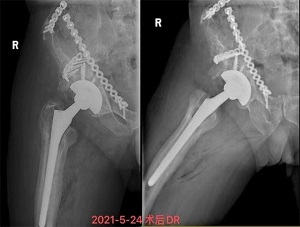

5月13日,饱受关节疼痛困扰的严爷爷在家人陪同下到我院就诊并入住关节骨病科。董克芳主任团队在仔细评估讨论后,制定了详细手术方案,并于5月21日为严嗲嗲进行了右人工髋关节翻修术,术后当日即指导其开始进行功能锻炼,1周后,严爷爷可下地行走,关节疼痛感也没了。28日,主管医生林少如反复叮嘱老人家一些注意事项后,严爷爷在家人陪同下出院回家了。